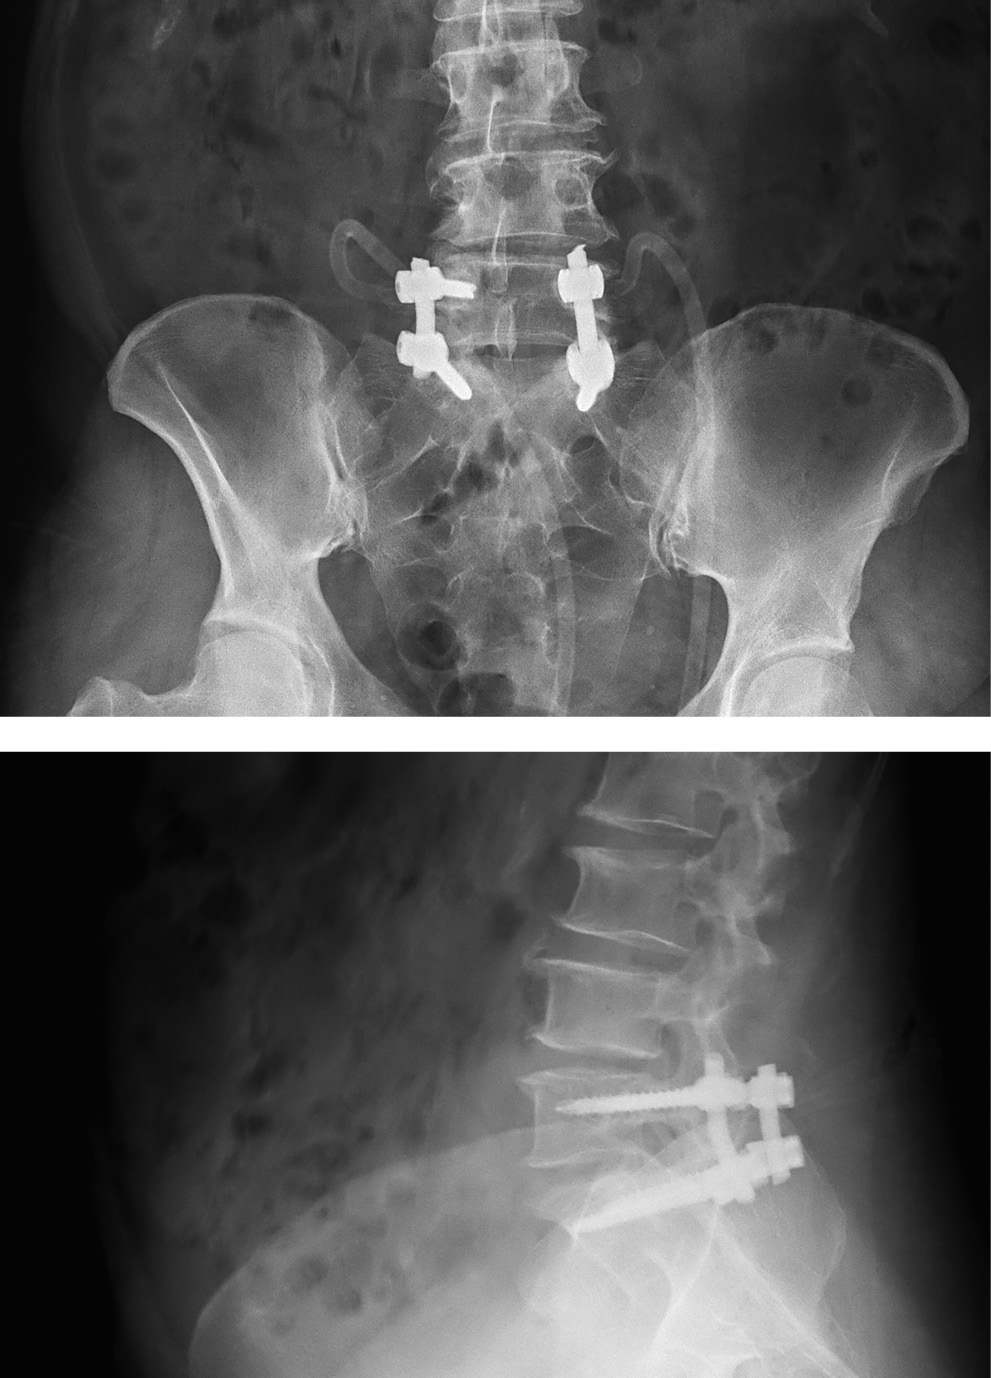

МРТ поясничного отдела позвоночника (рис. 1, 2): дегенеративно-дистрофические изменения пояснично-крестцового отдела позвоночника — 3-й период. Позвоночный канал деформирован на уровне LV-SI слева с сужением резервного эпидурального пространства и стенозированием левых латеральных отделов позвоночного канала на ширину до 0,3 см. Слева в промежутке LV-SI визуализируется образование с ровными четкими контурами, гиперинтенсивного сигнала в Т2и гипоинтенсивного сигнала в Т1-режимах, размером 14×8×8,5 мм. Прослеживается связь образования с дугоотростчатым суставом. Киста пролабирует из полости сустава в позвоночный канал по левому боковому карману, приводя к стенозу и компрессии спинномозговых корешков на уровне LV-SI.

Рис. 1. Пациентка C.: МР-томограмма поясничного отдела позвоночника в T2-режиме в сагиттальной (а) и аксиальной (б) проекциях. Аксиальная проекция выполнена на уровне диска LV-SI (стрелкой указана периартикулярная фасеточная киста)

Важно отметить, что на фронтальных МРТ-сканах периартикулярная киста компримирует спинномозговой корешок SI. Прослеживается расположение кисты в латеральном канале, где отмечается щелевидная полость, которая сообщается с полостью фасеточного сустава.

Рис. 4. Контрольные спондилограммы пациентки С.